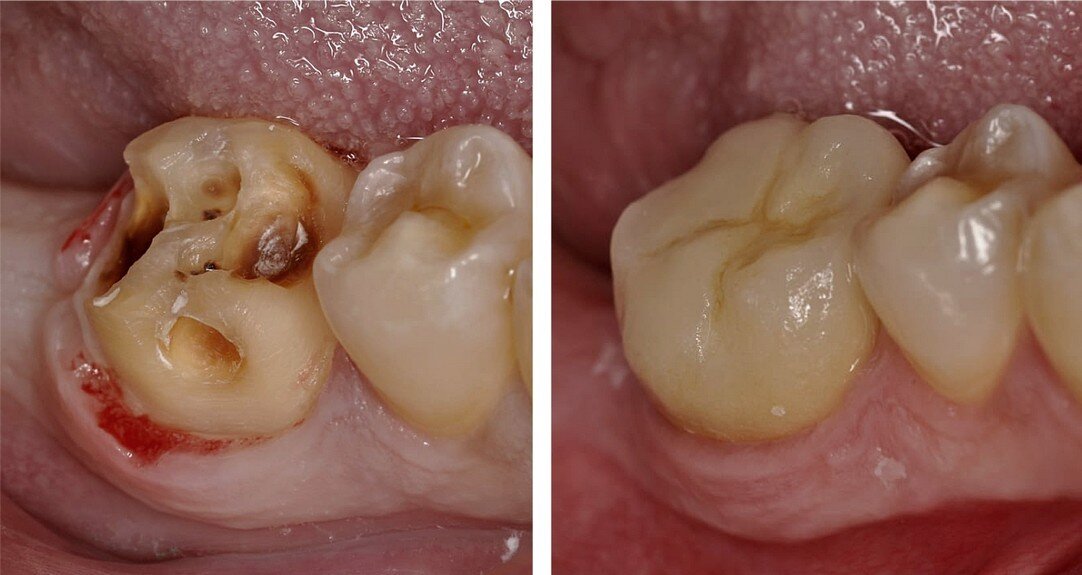

Фото: «УстаДент»